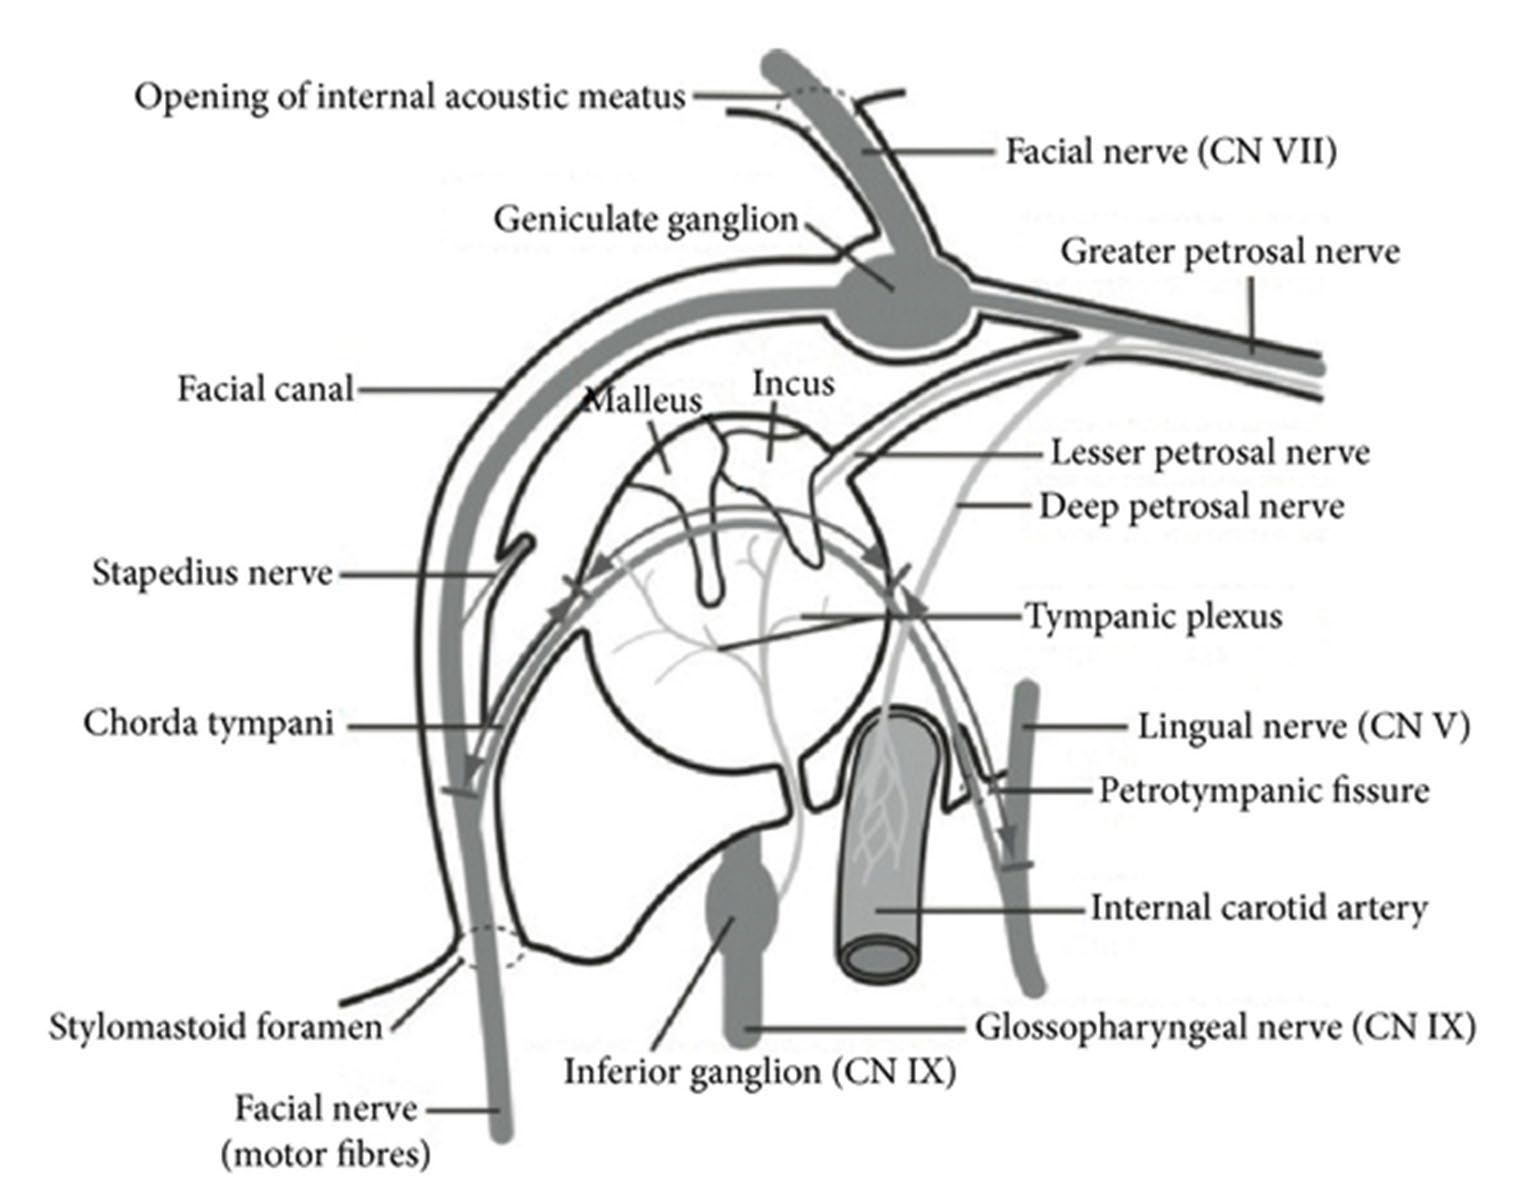

CN VII

Greater petrosal n.(Parasymphysis)

- Mucous g.

- Lacrimal g.

Stapedius n.

- 支配Stapedius m.

Chorda Tympanic n.(Parasymphysis)

- 支配前味覺

- Submandibular, Sublingual g.

Chorda tympanic

CN IX

- Lesser petrosal n.(Parasymphysis)

- 支配Parotid g.的副交感節前神經

- Tympanic n.

- 中耳、鼓膜內面、耳咽管(Eustachian)